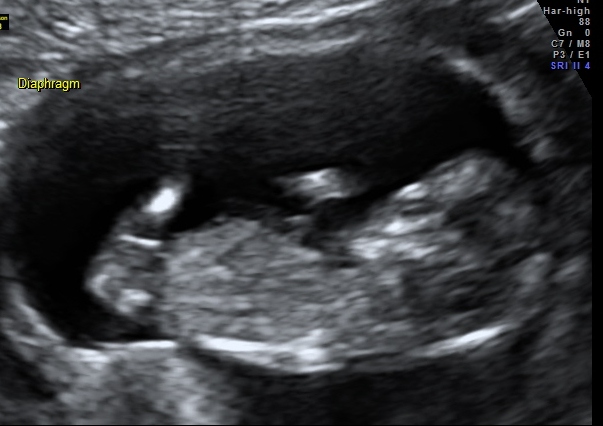

Well this little one has a very boy-ish head but I'm not sure what to make of the nub, if that's vene a nub captured in the images. Any guesses would be much appreciated.

I am gonna lean blue. The angle is not very much when you follow the spine curve, but it's got a bobble on the end that makes me think it might be rising. But it's a close call for me.

Baby looks slightly turned away so I wouldn't be surprised either way. My first thought was pink, though.

Pic 1 makes me think boy but Pic 2 looks pretty girly so I am saying 60/40 girl lean.

In the second pic I think the nub looks girly, so I would lean pink. I wouldn't focus too much on skull shape because the head is a bit distorted in these images and also looks like head is turned sideways.